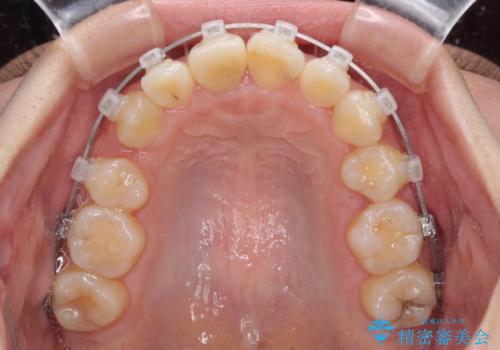

- 矯正装置

- クリアブラケット

口元の突出感は少なく、下顎の叢生は軽微なものであったので、叢生の強い上顎左右の小臼歯を1本ずつ抜歯し、ワイヤー装置にて矯正治療を行うこととしました。

矯正治療を行う前に、根管治療の必要な上顎前歯と下顎大臼歯の根管治療を行い、矯正治療の途中で下顎の欠損部にインプラント埋入することとし、矯正治療後に補綴治療を行うこととしました。

矯正治療中にインプラント埋入を行うなど、余計な時間や無駄のない治療を行うことができました。